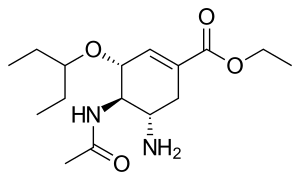

IUPAC name

| Formula | C16H28N2O4 |

| Molar mass | 312.410 g·mol−1 |

SMILES

InChI

Mechanism of action

Oseltamivir is a neuraminidase inhibitor, a competitive inhibitor of influenza's neuraminidase enzyme. The enzyme cleaves the sialic acid which is found on glycoproteins on the surface of human cells that helps new virions to exit the cell. Thus oseltamivir prevents new viral particles from being released.[26]